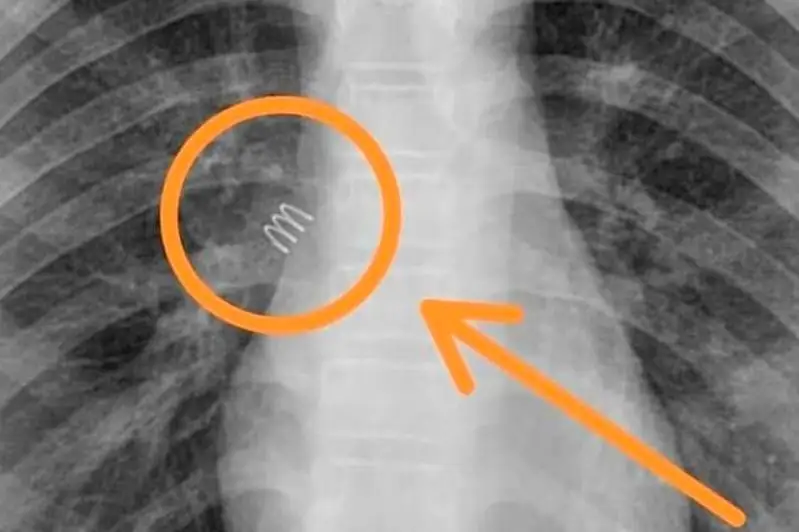

Пружину удалили из бронхов 11-летней девочки в Актау